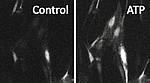

In a healthy brain, the BBB prevents neural tissue from the invasion of pathogens, the infiltration of immune cells and extravasation of serum proteins. In addition, brain cells have a high demand for glucose, oxygen, and other factors, coming from the blood. The perfusion with blood is tightly regulated in terms of time and localization. In this process different cell types, including neurons, astrocytes, pericytes, smooth muscle cells, and endothelial cells, are activated and all of them are able to influence the kinetics and amplitude of perfusion. If the communication between these cells is dysregulated as in stroke, dementia, diabetes, or obesity, also vascular reactivity is altered.

We are interested in intercellular connections, especially in those that involve endothelial cells, and in the effects of endothelial dysfunction on related brain functions. For this purpose we are using state-of-the-art technologies like two-photon microscopy, tissue-specific knockout animal models, and virus-mediated gene transfer.